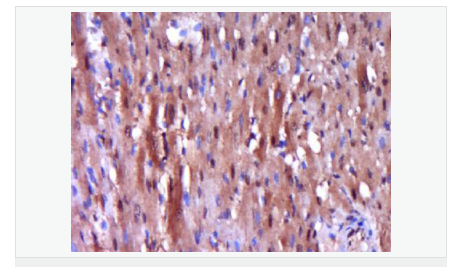

| 產(chǎn)品應(yīng)用 | WB=1:500-2000 ELISA=1:5000-10000 IHC-P=1:100-500 IHC-F=1:100-500 Flow-Cyt=1ug/Test ICC=1:100 IF=1:100-500 (石蠟切片需做抗原修復(fù)) not yet tested in other applications. optimal dilutions/concentrations should be determined by the end user. |

| 產(chǎn)品介紹 | Caspase 9 (also known as ICE like apoptotic protease 6 (ICE LAP6), apoptotic protease Mch6, and apoptotic protease activating factor 3 (Apaf3)) is a member of the peptidase family C14 that contains a CARD domain. This caspase is active as a heterotetramer and has been reported to have two isoforms. ProCaspase 9 has been reported to be approximately 47 kD. This caspase is present in the cytosol and, upon activation, translocates to the mitochondria. Caspase 9 is involved in the caspase activation cascade responsible for apoptosis execution and cleaves/activates Caspase 3 and Caspase 6. Caspase 9 is inhibited by the dominant negative isoform, BclXL, cIAP1, cIAP2, XIAP, and Livin. This caspase becomes activated when recruited to Apaf1/cytochrome c complex, and following cleavage by Apaf1, granzyme B, Caspase 3, possibly Caspase 8 and Caspase 10 into large p37 and small p10 subunits. Caspase 9 intereacts with BIRC7 and has been shown to cleave PARP and vimentin. Function: Involved in the activation cascade of caspases responsible for apoptosis execution. Binding of caspase-9 to Apaf-1 leads to activation of the protease which then cleaves and activates caspase-3. Proteolytically cleaves poly(ADP-ribose) polymerase (PARP). Isoform 2 lacks activity is an dominant-negative inhibitor of caspase-9. Subunit: Heterotetramer that consists of two anti-parallel arranged heterodimers, each one formed by a 35 kDa (p35) and a 10 kDa (p10) subunit. Caspase-9 and APAF1 bind to each other via their respective NH2-terminal CED-3 homologous domains in the presence of cytochrome C and ATP. Interacts (inactive form) with EFHD2. Interacts with HAX1. Interacts with BIRC2/c-IAP1, XIAP/BIRC4, BIRC5/survivin, BIRC6/bruce and BIRC7/livin. Tissue Specificity: Ubiquitous, with highest expression in the heart, moderate expression in liver, skeletal muscle, and pancreas. Low levels in all other tissues. Within the heart, specifically expressed in myocytes. Post-translational modifications: Cleavages at Asp-315 by granzyme B and at Asp-330 by caspase-3 generate the two active subunits. Caspase-8 and -10 can also be involved in these processing events. Phosphorylated at Thr-125 by MAPK1/ERK2. Phosphorylation at Thr-125 is sufficient to block caspase-9 processing and subsequent caspase-3 activation. Similarity: Belongs to the peptidase C14A family. Contains 1 CARD domain. SWISS: P55211 Gene ID: 842 Database links: Entrez Gene: 842 Human Entrez Gene: 12371 Mouse Omim: 602234 Human SwissProt: P55211 Human SwissProt: Q4FJK5 Mouse Unigene: 329502 Human Unigene: 88829 Mouse Unigene: 32199 Rat Important Note: This product as supplied is intended for research use only, not for use in human, therapeutic or diagnostic applications. Caspase-9半胱氨酸蛋白酶家族成員之一,又稱ICE-Lap6(ICE Like apoptotease 6)參與細胞凋亡過程和細胞因子的加工過程,在許多胚胎和成人組織中都有分布。此抗體主要用于腫瘤研究。 |